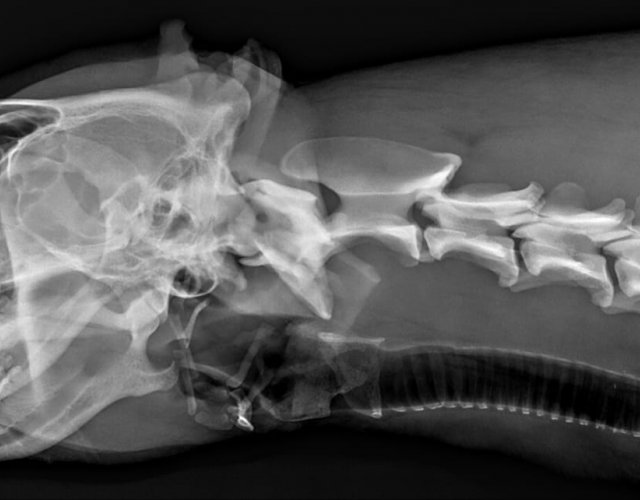

Pe strada Cocorilor a avut loc un accident grav in timp ce un caine fugarea o pisica. Amandoi au fost loviti de o masina. Pisica a decedat pe loc. Cainele si-a pierdut ambii ochi si are bazinul fracturat in mai multe locuri. In urma analizelor am constatat ca are si viermi cardiaci. Fiind fracturat si osul sacrum, a ramas paralizat si a trebuit eutanasiat datorita ranilor de decubit si a incontinentei.